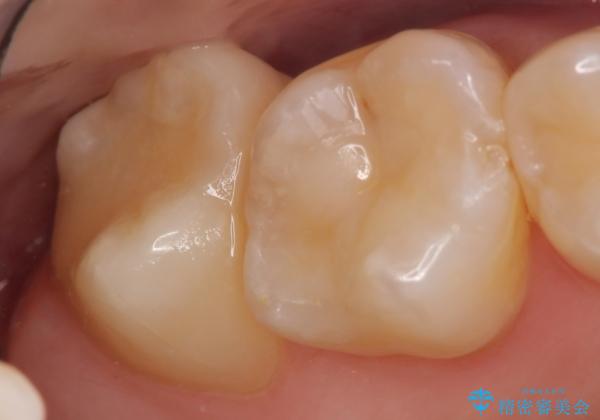

- 冷たいものを飲むと右上の奥歯がしみるので診て欲しいといらっしゃった方の症例です。

右上6番目、7番目の歯の樹脂が劣化していたため、虫歯除去後セラミックインレーによる修復を行いました。

当院のセラミックインレーはemaxという強度と審美性に優れた材料を使用しています。

またプレス方式でインレーを製作しているため、削り出しで製作するCADCAMより優れた適合性も持ち合わせており、虫歯が再発しにくい修復物です。